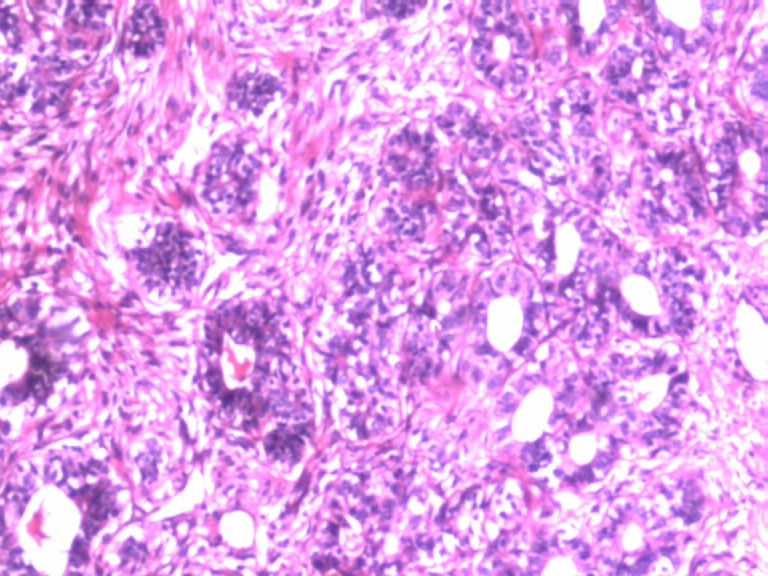

• 乳腺肿物图3

图3

患者,女,29岁,右侧乳腺肿物一个月。切面淡黄,均匀一致,质中。

标签:乳腺管状腺瘤

有肌上皮而且有的地方还有肌上皮增生,应该是腺病,你应该多采些低倍镜的图像,高倍镜的大多了没有太大的意义。

病变组织小叶结构未见,见管状、盲管状的腺管,周围似有空亮的肌上皮,腺上皮可见细小的核仁,染色质均细,导管上皮普通型增生。有包膜为盲管状腺瘤,则为腺病。